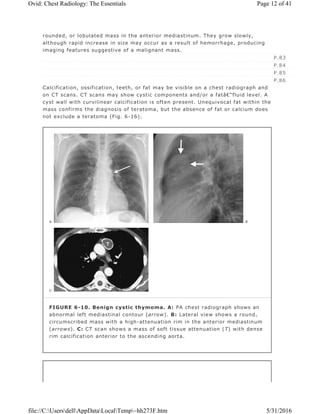

FIGURE 6-10. Benign cystic thymoma. A: PA chest radiograph shows an

abnormal left mediastinal contour (arrow). B: Lateral view shows a round,

circumscribed mass with a high-attenuation rim in the anterior mediastinum

(arrows). C: CT scan shows a mass of soft tissue attenuation (T) with dense

rim calcification anterior to the ascending aorta.

appear cystic with discrete nodular components (Figs. 6-10 and 6-11). In